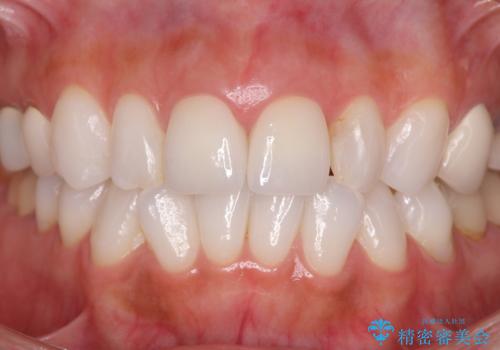

歯の大きさの不揃いが改善されただけでなく、色調もよくなり審美性をしっかりと改善することができました。